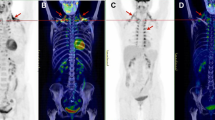

Based on PET/CT data of cohort 1 (Fig. 3a,b), subjects were initially divided into a ‘low BAT’ (mean SUV (SUVmean)<median SUV [2.70]) and ‘high BAT’ (SUVmean>median SUV [2.70]) group (n=11 per group; Table 1). Interestingly, serum exosomal miR-92a abundance was significantly lower in the high BAT group compared with the low BAT group (unpaired, two-tailed t-test, P=0.017, Fig. 3b), whereas miR-133a abundance was similar between groups (unpaired, two-tailed t-test, P=0.757, Supplementary Fig. 3a). In addition, when considering the group as a whole, we observed a significant negative correlation between Log10 miR-92a and the BAT SUVmean value (Fig. 3c). Such correlation was absent for miR-133a (Supplementary Fig. 3b). In a stepwise multivariable linear regression analysis with Log10 miR-92a as a dependent variable, and age, sex, BMI, fat mass and BAT SUVmean, SUVmax and glucose uptake rate as independent variables, all three BAT parameters were significant predictors of Log10 miR-92a (Supplementary Table 6). In addition, individual univariate analyses showed no relations between other parameters and Log10 miR-92a. As alternative to BAT SUVmean, we also assessed BAT SUVmax and glucose uptake rate (Fig. 3d,e). In both cases, we observed a significant correlation between these values and the Log10 miR-92a value (SUVmax: Pearson’s correlation, R2=0.28, P=0.011, glucose uptake rate: Pearson’s correlation, R2=0.26, P=0.016, n=22), (Fig. 3d,e, respectively). Furthermore, to rule out that single axis logarithmic transformation resulted in such linear correlations, we performed similar analysis for the Log10 BAT SUVmean−Log10 miR92a (Pearson’s correlation, R2=0.18, P<0.05, n=22), as well as the Log10 BAT SUVmax−Log10 miR92a (Pearson’s correlation, R2=0.25, P<0.05, n=22), which resulted in similar correlations (Supplementary Fig. 3c,d, respectively).

(a) 18F-FDG PET/CT image of a subject with high (brown) and low (blue) BAT activity. (b) miR-92a expression as quantified by qPCR. Subjects were separated into two groups with high and low BAT activity. Data is normalized to U6, and expressed as mean±s.e.m. (unpaired, two-tailed t-test, *P<0.05, n=11 per group). (c) Log10 miR-92a value is negatively related to BAT SUVmean value when considering the whole group. The obtained correlation equation is: BAT SUVmean (predicted)=−0.8749 × Log10 miR-92a+3.5227, (Pearson’s correlation, R2=0.26, P=0.015, n=22). (d) Log10 miR-92a value is negatively related to BAT SUVmax (Pearson’s correlation, R2=0.28, P=0.011, n=22). (e) Log10 miR-92a value is negatively related to BAT glucose uptake rates (Pearson’s correlation, R2=0.26, P=0.016, n=22). (f) Changes in miR-92a expression levels (ΔLog10 miR-92a value) tended to correlate with changes in BAT activity (Delta BAT SUVmean value) on a 10-day cold acclimation period (Pearson’s correlation, R2=0.29, P=0.11; n=10; and Supplementary Table 3). (g) Log10 miR-92a is elevated in individuals without BAT activity (unpaired, two-tailed t-test, **P=0.01, n=6 for no detectable BAT and n=13 for subjects with detectable BAT). (h) Log10 miR-92a value is negatively related to BAT glucose uptake rates in a second cohort (Pearson’s correlation, R2=0.40, P=0.004, n=19).

Ten subjects were subsequently exposed to a 10-day cold acclimation period, which caused a recruitment of BAT and an increase in non-shivering thermogenesis, as described previously35. Interestingly, miR-92a abundance tended to be lower after this cold acclimation period (19.5±12.9 versus 13.6±12.7) and the change in miR-92a levels tended to be negatively related to changes in BAT activity (Pearson’s correlation, R2=0.29, P=0.11, Fig. 3f) on this cold acclimation period. In addition, the regression equation obtained in Fig. 3d correctly predicted whether subjects would either show a large increase (>change in median SUVmean [+0.43]) or a small increase/decrease (< change in median SUVmean) in BAT activity on cold acclimation, based on changes in miR-92a (Supplementary Table 3). The prediction was correct in 8 out of 10 cases with a considerable variation (confidence intervals 0.44 to 0.97 (exact interval)) (Supplementary Table 3). Interestingly, two patients in this cohort did not show BAT activity (BAT SUVmean was 0.37 or 0.45 in these subjects, respectively) along with high serum level of miR-92a (Fig. 3f, Supplementary Tables 3 and 4). One individual participating in the cold acclimation study showed a large decrease in miR-92a after cold-exposure along with high increase in BAT activity (ΔBAT SUVmean=1.59, Supplementary Table 3).

Moreover, we analysed miR-92a levels in serum exosomes in subjects (in 15 out of the 22 subjects blood samples were available; Supplementary Tables 3 and 4) that were acutely exposed to cold (ca. 1–1.5 h). Serum Log10 miR-92a levels of these acute cold-exposed subjects also tended to inversely correlate with BAT SUVmean (Pearson’s correlation, R2=0.21, P=0.08, n=15, Supplementary Fig. 3e). No blood was withdrawn from seven patients due to vasoconstriction in cold (Supplementary Tables 3 and 4).

To verify the observed correlation of exosomal miR-92a with BAT activity, we investigated cohort 2 (19 individuals) with a wider range of BMI (from 18.9 to 28.9) and age (from 21 to 51) that were also analysed by 18FDG-PET/CT (Supplementary Table 5). The correlation analysis of Log10 miR-92a as a dependent variable, and age, sex, BMI, fat mass and glucose uptake rate as independent variables identified glucose uptake rate as only significant predictor of Log10 miR-92a (Supplementary Table 7). Interestingly, exosomal miR-92a abundance was significantly higher in individuals that were BAT negative compared with those with detectable BAT tissue (Fig. 3g). Similar to cohort 1, we observed a correlation between Log10 miR-92a and BAT activity (glucose uptake rate) (Pearson’s correlation, R2=0.40, P=0.004, n=19) (Fig. 3h). Taken together, exosomal miR-92a is an indicator of human BAT activity in the investigated two cohorts.